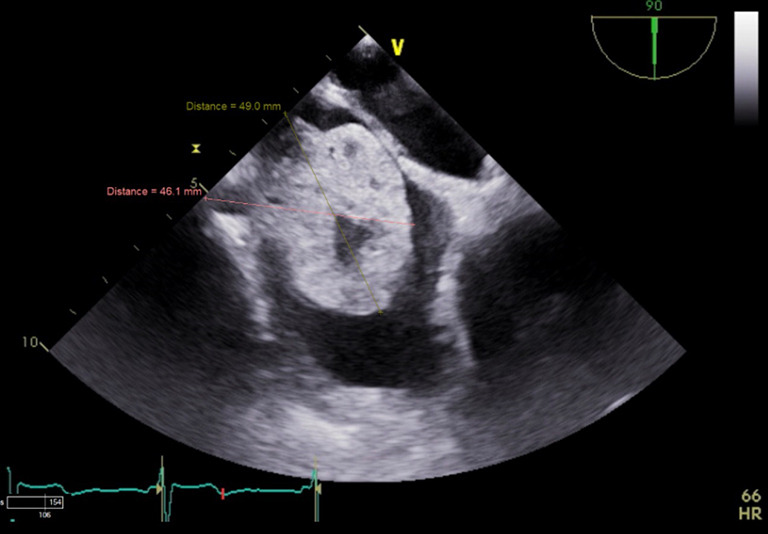

Case description: We present a case of a 65-year-old male who presented to the hospital with syncope, and was subsequently diagnosed with a level four cavoatrial sinus tumor thrombus extending from a primary renal mass. The patient had no concerning physical exam and electrocardiogram (EKG) findings, however, transthoracic and transesophageal echocardiography revealed severely reduced systolic function with a hyperechoic, vascular, and cystic mass extending from the IVC into the right atrial cavity that originated from a renal mass that involved the right renal vein and IVC.